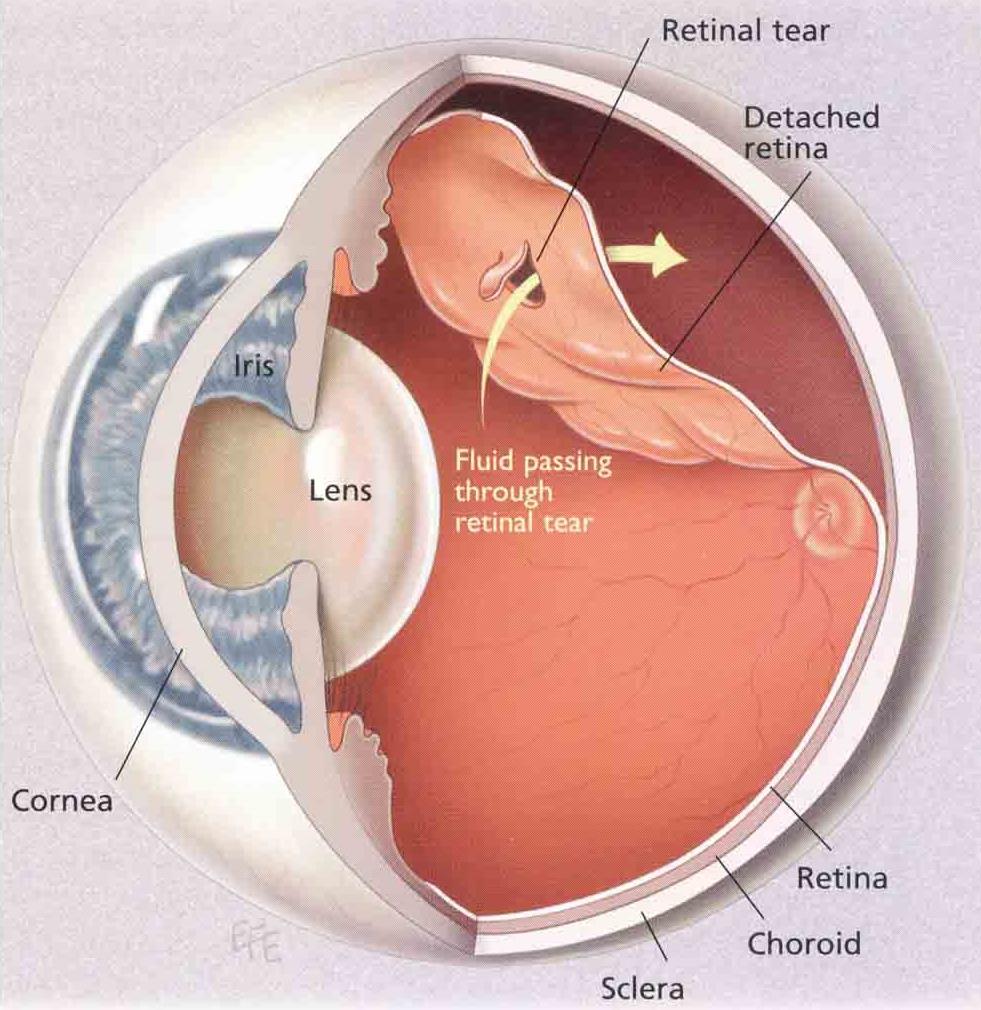

Intravitreous Gas Bubbles Retina Image Bank